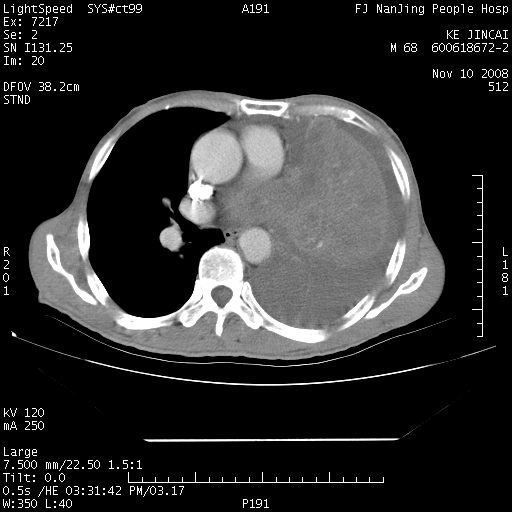

是个很有看头的病例,咋人气那么不旺?没多少人兴趣呢?这个病例几大怪:1   恶性肿瘤侵犯心肌左房怪,心肌一般不会被恶性肿瘤侵犯吧?2   左下肺均匀实变怪,内无含气,有别一般不张实变,含气肺泡完全为液体取代,而非一般不张实变的肺萎陷,冷不丁还以为是肿大的脾脏3   肿瘤本身怪,像tb肺不张4   这么有看头的病例没人气怪。呵呵。

左肺恶性肿瘤侵犯肺动脉,左心房内瘤栓,胸膜转移。

左肺恶性肿瘤侵犯肺动脉,左心房内瘤栓,胸膜转移,少见,学习了。